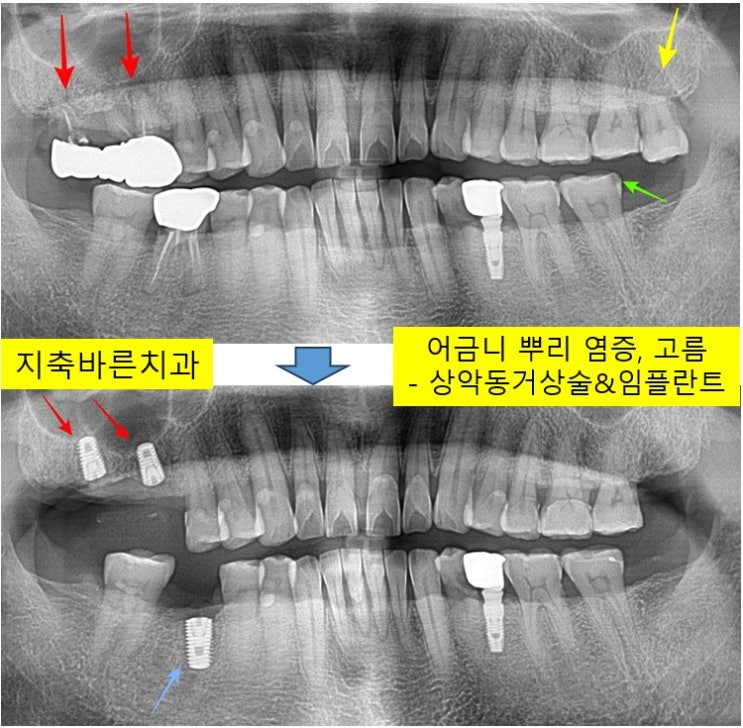

잇몸이 불편하고, 임플란트 상담을 원하신다며 2024년 1월 50대 Mㅁㅁ 님께서 내원해주셨습니다. 1. 처음 ...